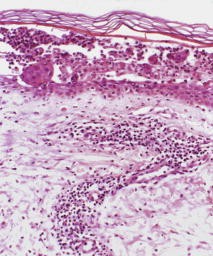

Der IgA-Pemphigus ist eine seltene, intraepidermale Autoimmundermatose, die durch interzelluläre IgA-Ablagerungen, intraepidermale Akantholyse mit Neutrophileninfiltration und zirkulierenden IgA-Autoantikörpern gegen Oberflächenstrukturen der Keratinozyten gekennzeichnet ist. Wir berichten zum 1. Mal über einen Patienten mit einem aggressiv verlaufenden IgA-Pemphigus, bei dem eine Behandlung mit Mycophenolat mofetil zur Rückbildung der Hautveränderungen bei stabilem Krankheitsverlauf führte.

IgA pemphigus is a rare intraepidermal autoimmune disease characterized by the presence of intercellular IgA deposits, intraepidermal acantholysis with infiltration of neutrophils, and circulating IgA autoantibodies against keratinocyte cell surface components. We report for the first time about a patient with IgA pemphigus who was successfully treated with mycophenolate mofetil.